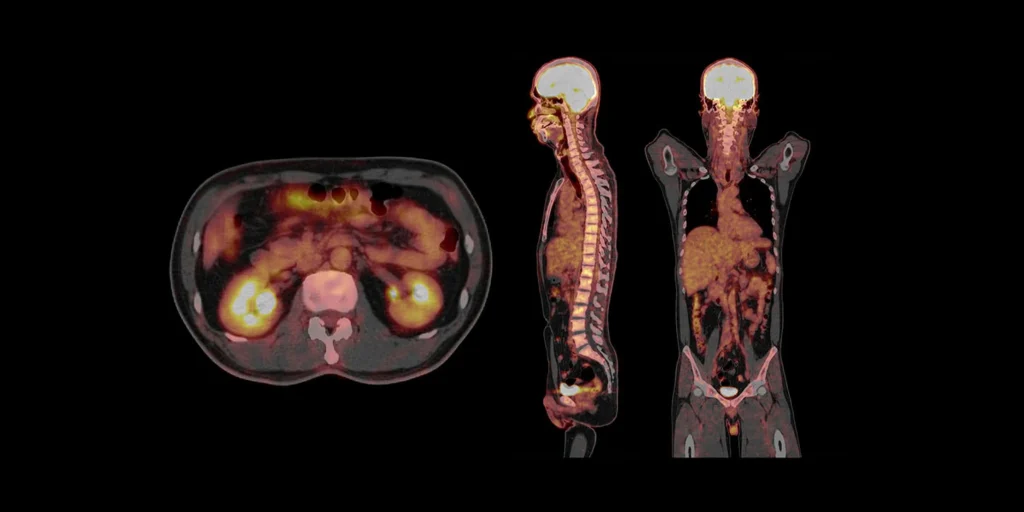

PET Scan: exame mais detalhado da dopamina

O PET com [18F]-DOPA ou [18F]-FP-CIT avalia com ainda mais precisão a produção e o transporte da dopamina.

- Pode detectar alterações em fases iniciais.

- No DIP, costuma estar normal.

Disponibilidade no Brasil: o PET Scan está disponível em alguns centros especializados, geralmente em grandes hospitais e clínicas de medicina nuclear, mas ainda com acesso restrito e custo elevado. É menos utilizado do que o DaTscan para diferenciar DIP de Parkinson no dia a dia.